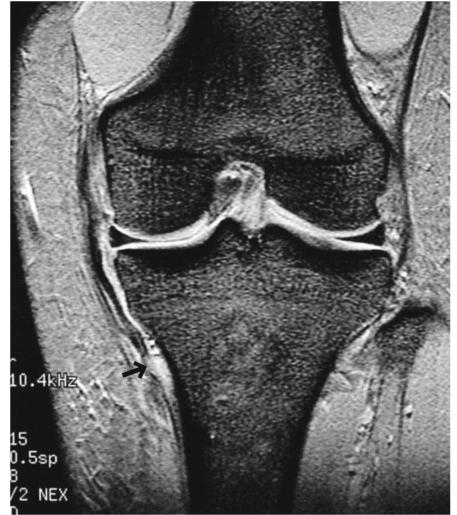

- 超过一半的MCL撕裂发生在近端(股骨)部分,但较少发生在远端(胫骨)部分(图5.10)。

图5.10远端(胫骨)部分撕裂。一个20多岁的女性。冠状T2*WI显示靠近胫骨附着点的MCL(箭头)表层撕裂